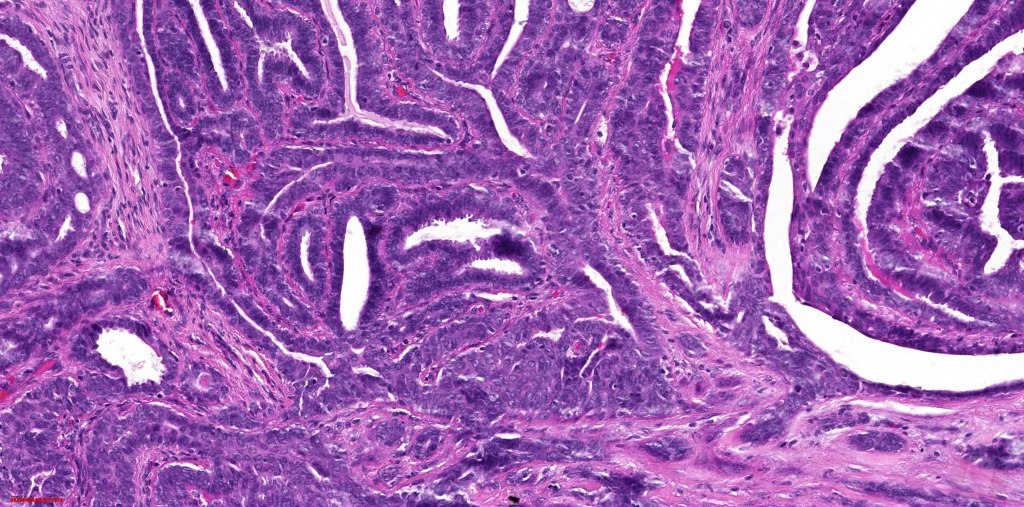

Histological features

•Papillae lined by myoepithelial cells with overlying epithelial cells with eosinophilic cytoplasm showing decapitation secretion

•+/- Oxyphil metaplasia

•Cribriform pattern sometimes evident

•Mitoses can be absent or even brisk

•No pleomorphism or abnormal mitoses

•No necrosis, lymphovascular invasion or perineural infiltration